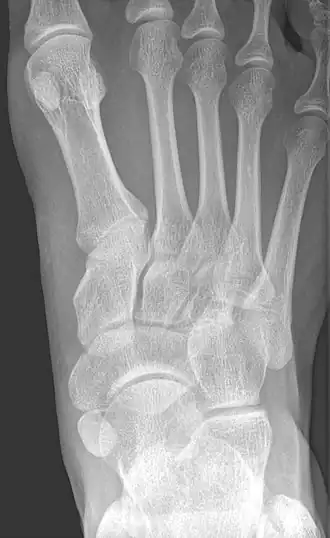

-

Type 2 -